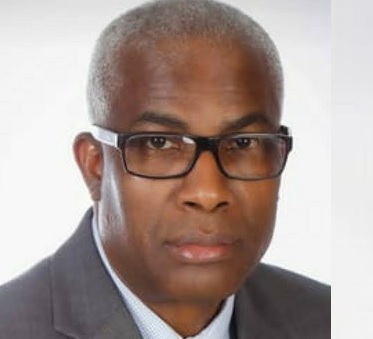

“Una pregunta fundamental en la investigación del Parkinson ha sido por qué mueren las células más vulnerables a la enfermedad”, indica el doctor Ken Nakamura, investigador del Instituto Gladstone de Enfermedades Neurológicas. “Responder a esta pregunta podría ayudarnos a comprender por qué se produce la enfermedad y a encontrar nuevas formas de tratarla”.

Para resolver ese enigma, el doctor Nakamura encabezó un equipo interdisciplinario de investigadores. Su más reciente estudio, publicado en la revista académica eLife, demuestra que una estimulación prolongada de las neuronas dopaminérgicas puede resultar en degeneración neuronal progresiva. En otras palabras, esta terrible enfermedad podría ser provocada por células cerebrales con burnout.